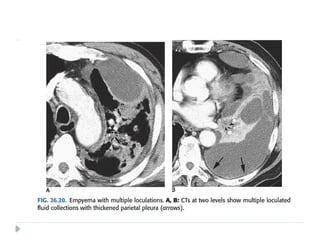

 Empyemas usually:

 form an obtuse angle with the chest wall

 unilateral or markedly asymmetric whereas pleural effusions

usually bilateral and similar in size .

 Biconvex , whereas pleural effusions are concave in shape

towards the lung.

 Features suggestive of an empyema on CT include:

 Enhancing thickened pleura ( split pleura sign) whereas

pleural effusion has thin imperceptible pleural surfaces

 locules of gas absent unless recent thoracocentesis

 Obvious septations

 Associated consolidation

 Associated adjacent infection (e.g. subdiaphragmatic abscess)